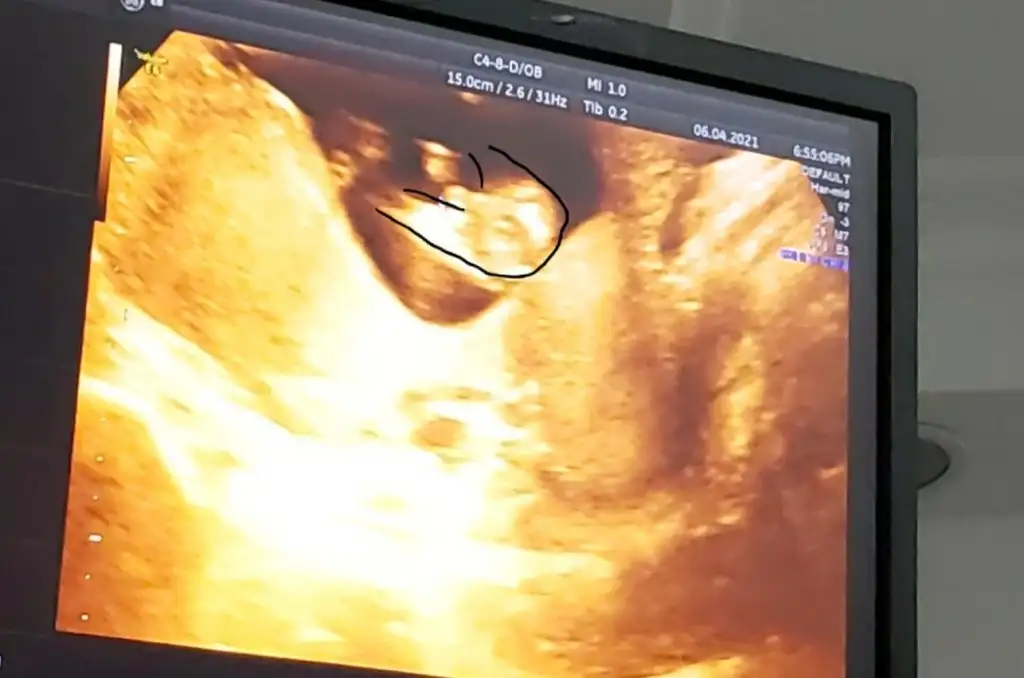

Üstte çizdim orası bacak gibi görünmedi okla gösterdiğim yer nub gibiAnladım sanırım o dqer bacaqının qörüntüsü 3 hafta sonra kesin belli olacaqını düşünüoruz 16 haftalık olucak ozman söylerim cinsiyetni inş nasipse